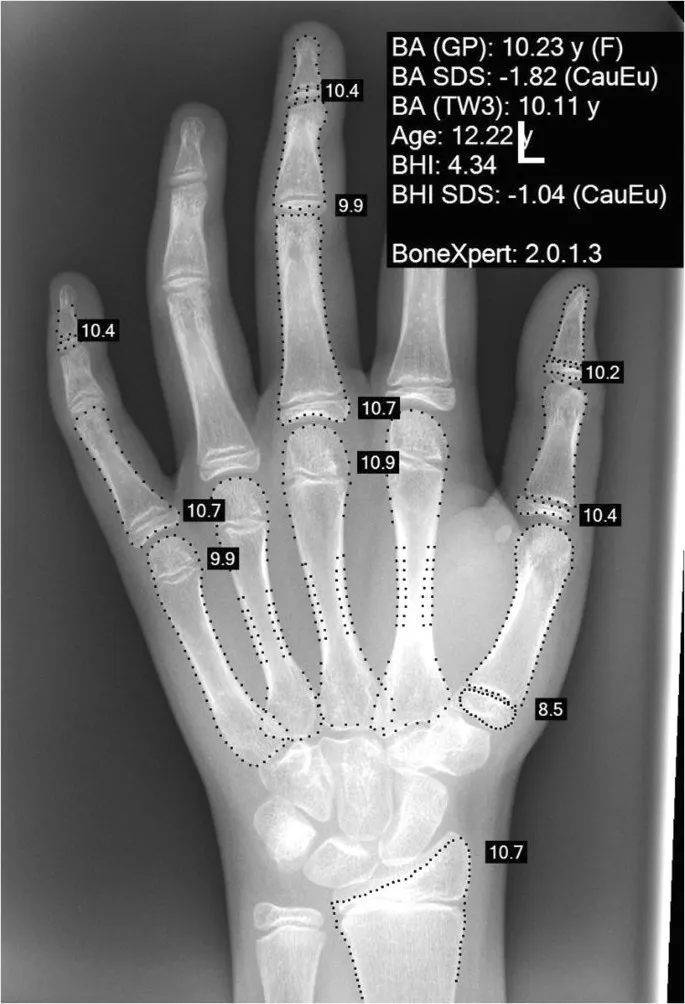

⭐ Bone age (X-ray of left hand & wrist) is the single most useful initial investigation to differentiate between normal variants (Familial Short Stature, Constitutional Delay) and pathological short stature.

⭐ The single most useful investigation in evaluating short stature is Bone Age estimation.

The goal is differentiating normal variants (FSS, CDGP) from pathology. The Bone Age is the most crucial first step.

- Bone Age: X-ray of left hand & wrist (Greulich-Pyle atlas). The key to diagnosis.

- Bone age is the single most crucial first step to differentiate between Familial Short Stature (FSS) and Constitutional Delay (CDGA).

- In FSS, Bone Age ≈ Chronological Age; the child follows the mid-parental height trajectory.

- In CDGA, Bone Age < Chronological Age; there is a history of delayed puberty.